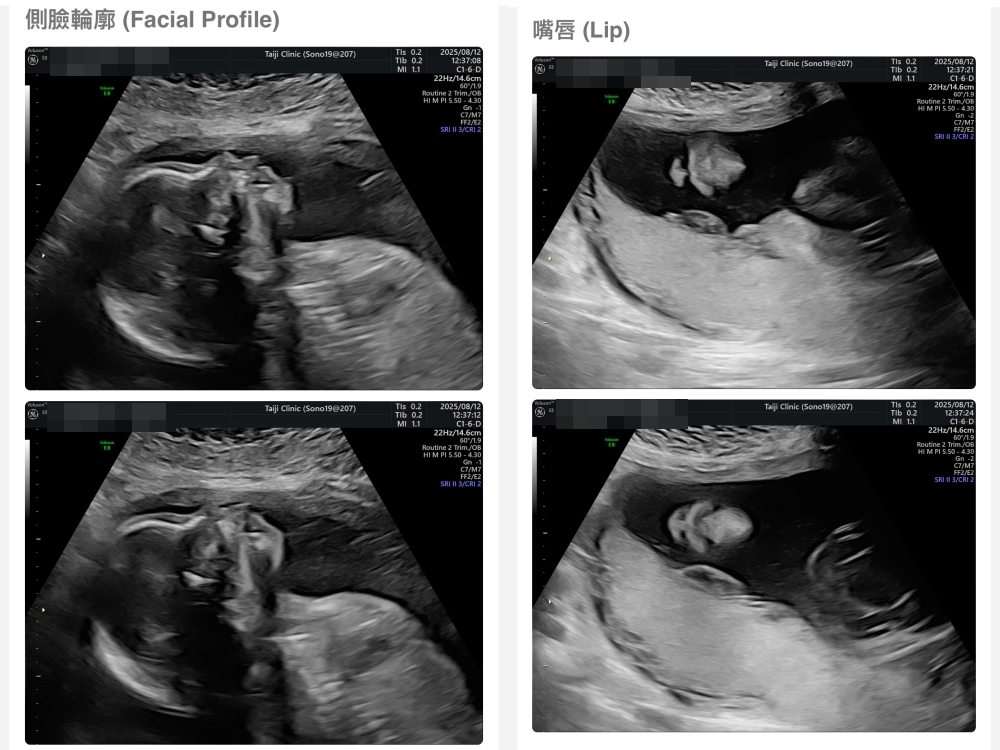

【台兒|高層次超音波|檢查結果】

▲離開診所後會收到MAIL,我們14:05離開,大約是16:45收到mail,裡面會有滿滿的超音波照片,紀錄的很詳細!也會提供紙本的報告,可以給日後產檢的醫師做參考👌